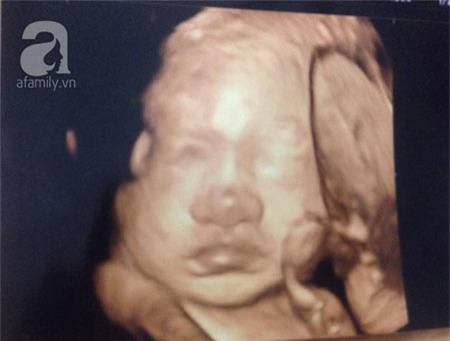

Vừa qua, BV Phụ sản TƯ đã xác nhận có tiếp nhận một 'thai phụ" ở Hòa Bình đến đăng ký sinh, nhưng khi siêu âm thì không thấy thai nhi. Theo những thông tin người nhà cung cấp thì sản phụ vẫn siêu âm định kỳ hàng tháng, lần siêu âm gần nhất ngày 1-3, em bé đạt 4 kg. Khi công an và gia đình có mặt, "thai phụ" mới thừa nhận đã mang thai giả suốt 9 tháng. Theo tìm hiểu của PV, người này vì sức ép quá lớn từ phía nhà chồng nên đã được sự hậu thuẫn của chính mẹ đẻ để mang thai giả. Cách đây khoảng 9 tháng, người phụ nữ này đi khám và nói cho chồng biết mình đã có thai. Cô vẫn đi siêu âm thường xuyên suốt 9 tháng thai kỳ.

Về thông tin người nhà cho hay, sản phụ trước đó đã có kết quả siêu âm thai nhi hơn 4kg, giám đốc bệnh viện khẳng định điều này hoàn toàn sai sự thật. Bác sỹ Quyết cũng cho rằng, chỉ có thể người này đánh tráo kết quả bằng cách nhờ người có bầu thật vào khám rồi khai tên của mình.